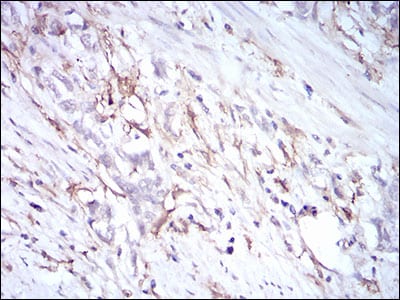

Immunohistochemical analysis of paraffin-embedded human stomach cancer tissues using CD72 mouse mAb with DAB staining.

Immunohistochemical analysis of paraffin-embedded Mouse kidney using CD72 mouse mAb with DAB staining.

Immunohistochemical analysis of paraffin-embedded Rat kidney using CD72 mouse mAb with DAB staining.

Immunohistochemical analysis of paraffin-embedded Rabbit kidney using CD72 mouse mAb with DAB staining.